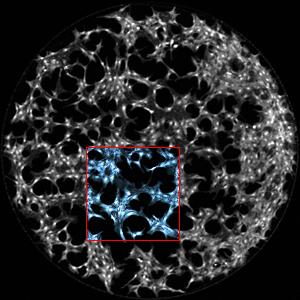

For example, the first drop might contain a hormone that tells cells to grow faster. Within seconds, this hormone sets off a chain reaction called a "phosphorylation cascade," modifying certain proteins within the cell in a specific sequence. To see these changes, scientists deliver a second drop containing formaldehyde, which freezes the all the proteins in place. They then deliver a third drop containing fluorescent antibodies that stick only to the proteins modified in the cascade. Looking at the antibodies in a microscope provides a snapshot of what has changed and what hasn't.

By building up a series of snapshots at different time intervals, scientists can see how the cascade progresses. "It's like a flipboard; each snapshot gives us a static image, but when you combine them all together, you can see movement or action," says Dean Chamberlain , a post-doctoral researcher at IBBME, the Donnelly Centre and the Department of Chemistry.

The team also made some interesting discoveries when they tested the technique on a type of breast cancer cells. "Roughly 10 per cent of the cells had a very rapid and strong response that we could detect up to five minutes before the rest of the population," says Chamberlain. The team speculates that these "rapid responders" may be involved in the early stages of tumour generation, although more research is needed to confirm this.